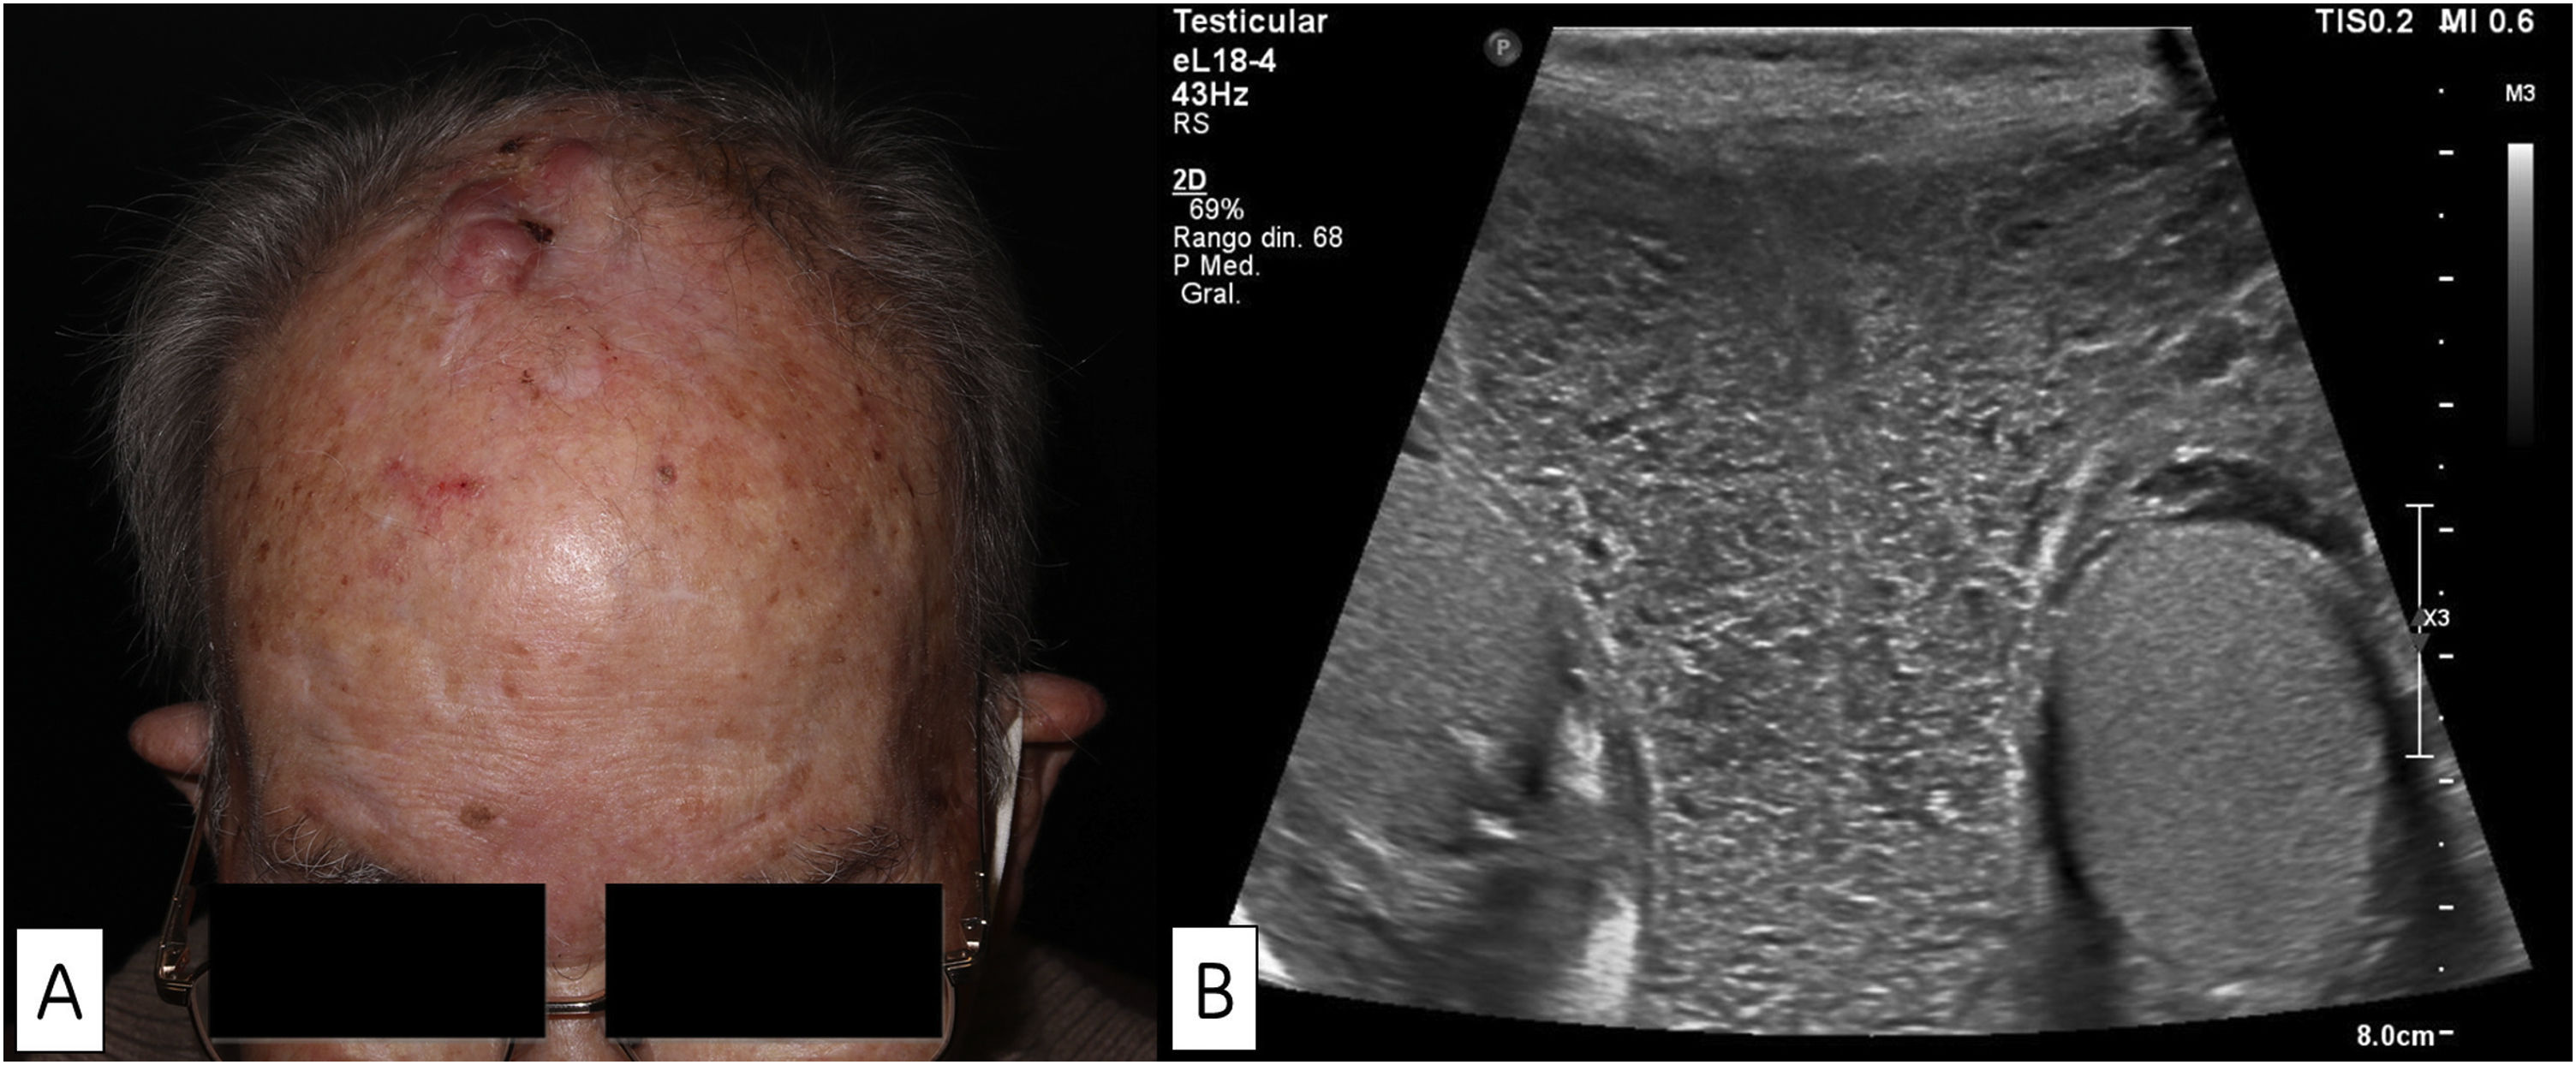

Diagnostic Challenges and Clinicopathologic Findings in Leg-Type Lymphoma: Retrospective Analysis of a Nine-Case Series